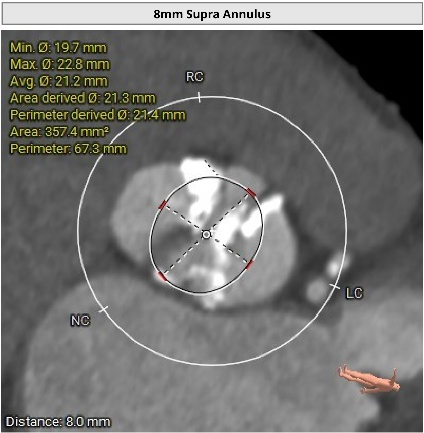

进一步评估显示,患者瓣膜狭窄程度重,瓣叶钙化明显,左心室腔径偏小,手术中对器械通过、瓣膜释放以及循环稳定性的要求都更高。团队结合术前影像和整体身体状况,制定了周密的介入治疗方案,并做好相关风险预案。

CT评估

瓣膜评估